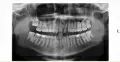

Иммедиат-протез представляет собой съемную временную конструкцию, которая призвана зафиксировать находящиеся рядом с удаленным зубы, пока не будет готов постоянный протез или коронка.

Иммедиат-протез выглядит как обыкновенный зуб, однако имеет по бокам крепления-клиперы в виде крылышек, откуда и пошло название «Бабочка».

Данными креплениями временный зуб фиксируется на своем месте и предотвращает повреждения десны в области удаленного зуба и выполняет эстетическую функцию. Чаще всего он применяется, если планируется ставить коронку или имплантат на передний зуб, поскольку даже временное его отсутствие приводит к значительным моральным неудобствам, особенно у женщин. Также не редко иммедиат-протез Бабочка ставится и на остальные. Разобравшись с тем, что это такое, давайте рассмотрим процесс изготовления иммедиат-протезов.